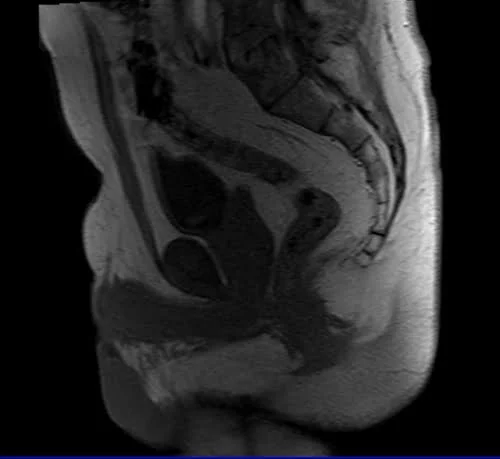

mri fistula localizer image 2 - MRI